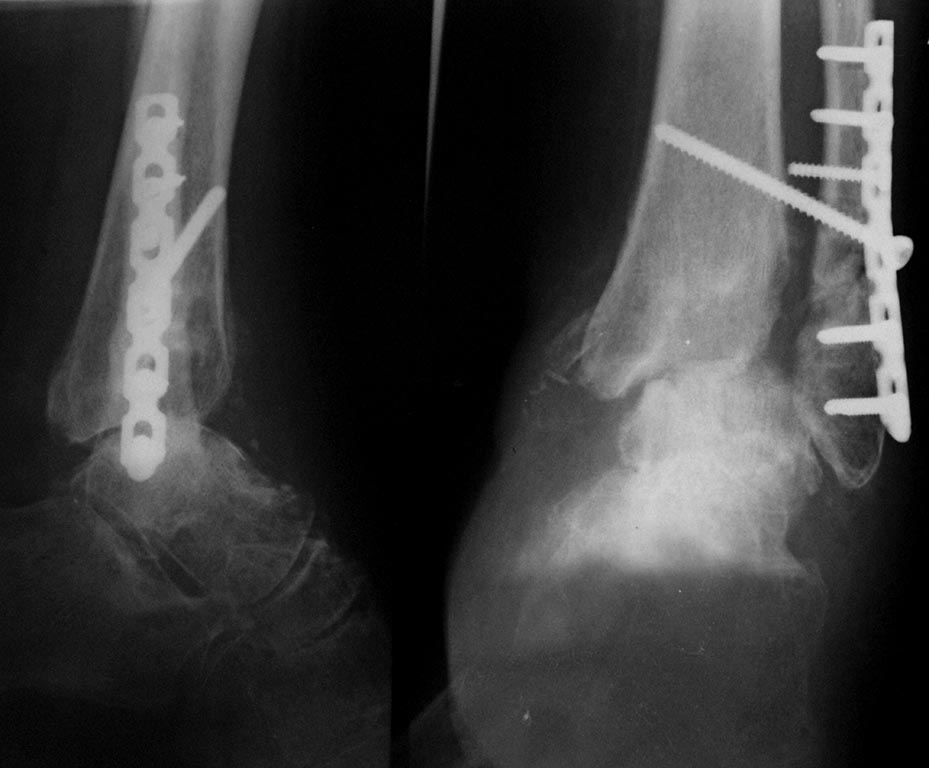

Уважаемые коллеги!Больная, 57лет, травма 2 года назад, переломы обеих лодыжек, выраженные фликтены, длительный(около месяца) предопер. период.

Неустраниимый подвывих стопы кнаружи и кзади. Открытая репозиция, синтез лодыжек, трансартикулярная фиксация спицами. Удаление спиц через 8 недель с рецидивом подвывиха. Повторная операция, трансартикулярная фиксация, вновь рецидив подвывиха. В июне 2013 года- ревизия голеностопного сустава, удаление свободных фрагментов суставной поверхности б/б кости, ревизия дельтовидной связки, устранение транспозиции сухожилия по медиальной лодыжке, устранение подвывиха, накостный синтез с установкой позиционного винта. Сегодня такая картина. Жалобы на постоянные боли. Сгибание -разгибание 10 градусов. Планируем резекцию суставных, артродез с фиксацией канюлированными винтами через пяточную кость. С последующей гипсовой иммобилизацией на 3 месяца. Раздумываю над АВФ. Хотелось бы узнать мнение о тактике, исходя из вашего опыта лечения таких больных. Спасибо.